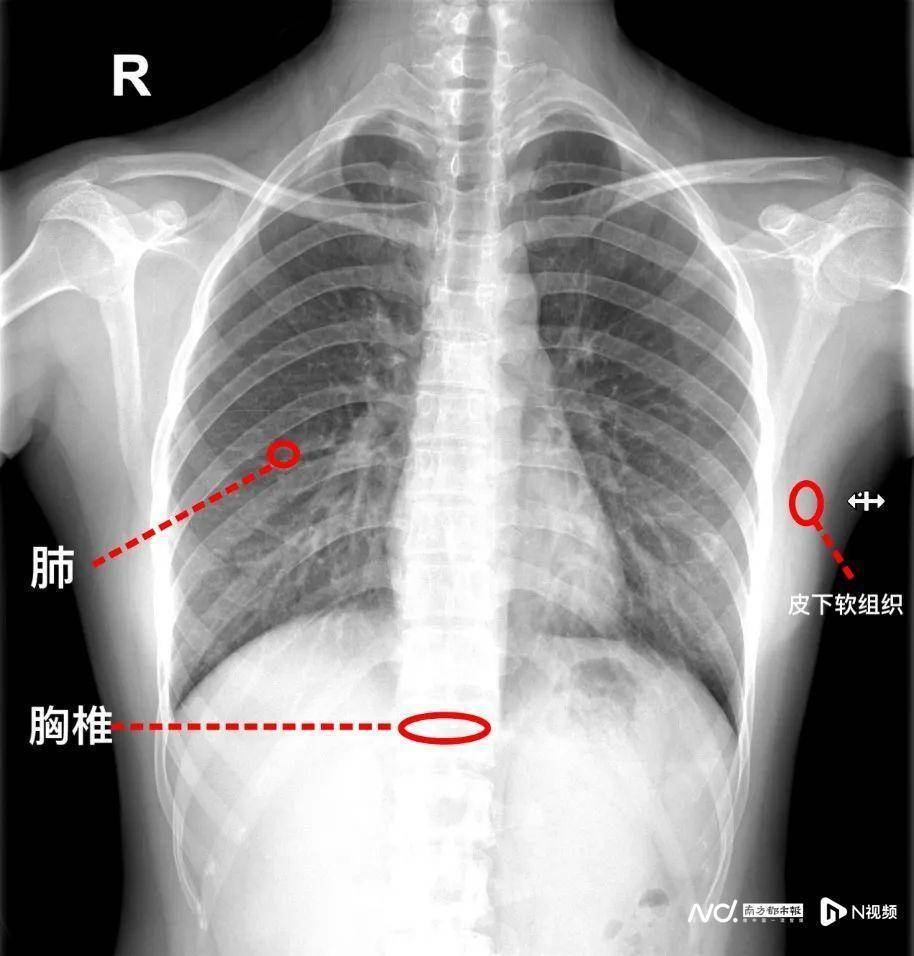

X线检查是利用射线成像,就像“透视眼”可以穿透人体,全部组织结构在同一平面上形成前后重叠的影像,且密度越低穿透能力越强,形成的图像越黑,密度越高穿透能力越低,形成的图像越白。

比如:肺充满气体,密度低容易被穿透,在X线片上显示出来就是黑色的;而骨骼密度高不容易被穿透,在X线片上显示出来就是白色的;而肌肉软组织穿透能力介于两者之间,在X线片上显示出来就是灰色的。

X线检查具有成像速度快、射线量低、价格相对低的特点,成为各种类型骨折、骨骼疾病、结石、肺部疾病等多种疾病的首选检查手段。

但是,由于X线片是很多器官重叠在一起的影像,因此X线对于一些复杂、重叠较多或细微结构的观察,不具有优势。